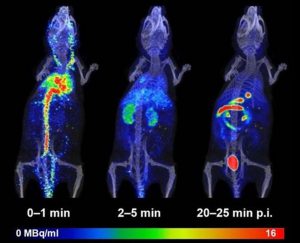

Image analysis is a critical component of clinical and preclinical imaging research, providing a means of quantifying and interpreting the data generated by imaging modalities such as PET, SPECT, and CT. In clinical imaging, image analysis is used to aid in diagnosis and treatment planning. For example, in oncology, image analysis can be used to assess the response to chemotherapy and radiation therapy, providing a means of monitoring the effectiveness of treatment and making adjustments as necessary.

In cardiology, image analysis can be used to evaluate blood flow and cardiac function, enabling the diagnosis and treatment of heart disease. In preclinical imaging research, image analysis plays a crucial role in the development of new treatments and therapies. Image analysis algorithms can be used to quantify the effects of drug treatments or surgical procedures on biological processes such as blood flow and metabolic activity. By providing a means of objectively assessing treatment efficacy, image analysis helps to optimize treatment protocols and improve patient outcomes.

The same image analysis techniques can be applied to both clinical and preclinical images, allowing for a seamless transition between research modalities. Moreover, image analysis has additional applications in clinical research, beyond the evaluation of disease progression or response to therapy. For example, image analysis can be used for radiation treatment planning to optimize the radiation dose and minimize side effects.

At our company, we provide a wide range of image analysis services for both preclinical and clinical imaging research. Our team of experts has extensive experience in conducting image analysis for various modalities, including PET, SPECT, CT, and optical imaging. We offer a comprehensive set of services, such as image registration, segmentation, quantification, and statistical analysis. We understand the importance of accurate and precise image analysis in the success of research projects, and we use state-of-the-art software and techniques to deliver reliable and reproducible results.